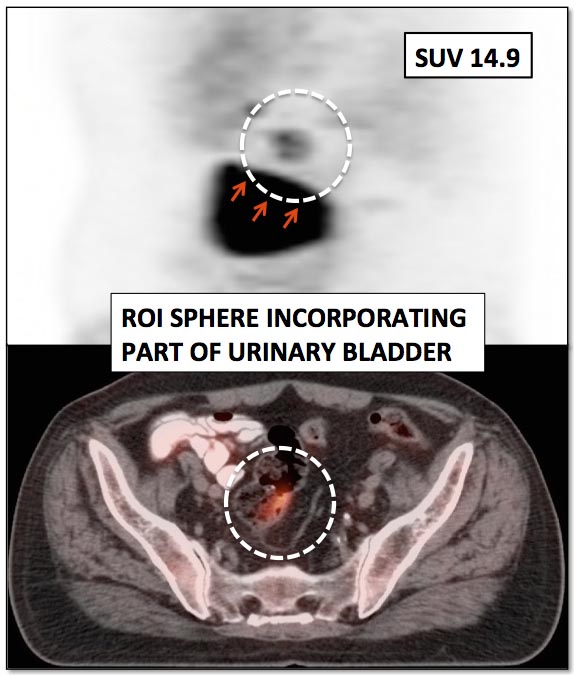

Size & Positioning of ROI:

When measuring an SUV, a region of interest (ROI) is drawn around the lesion. It is essential to assure that only the lesion is included in this ROI.

It is very easy to inadvertently include adjacent hypermetabolic structures in an ROI (frequently seen with lesions next to the heart, bladder, liver or brain), falsely increasing the measured SUV. [FIG. 8] [FIG. 9]